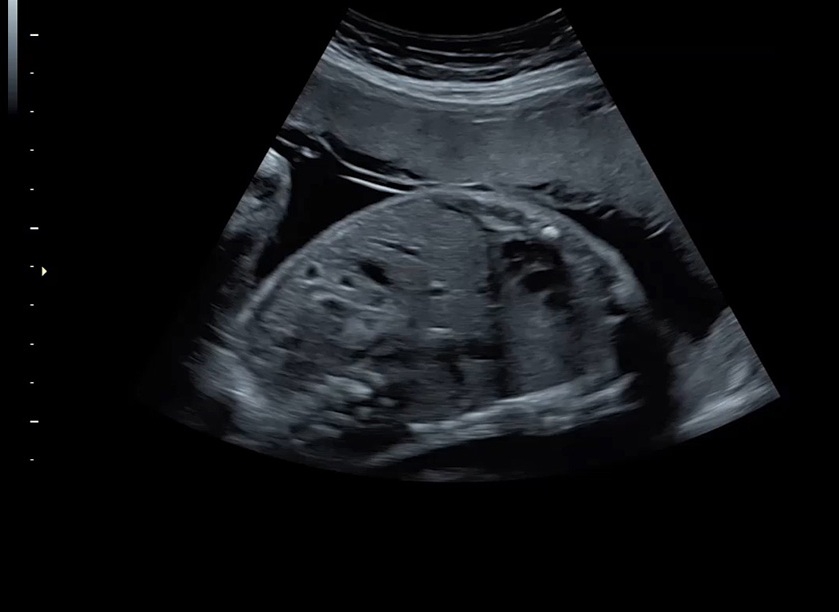

Ультразвуковая платформа Voluson S8 представляет собой оборудование экспертного класса с передовыми возможностями и высоким уровнем автоматизации процессов. Она позволяет проводить сканирование в режимах 2D, 3D и 4D с высоким качеством изображений.

• Высокое качество изображений: Voluson S8 обеспечивает высококачественные изображения, позволяющие детально оценить состояние плода и обнаружить возможные патологии.

• Высокочувствительные датчики: Ультразвуковой сканер Voluson S8 оснащен высокочувствительными датчиками, что позволяет проводить полноценное обследование даже у пациентов с сложными анатомическими особенностями.